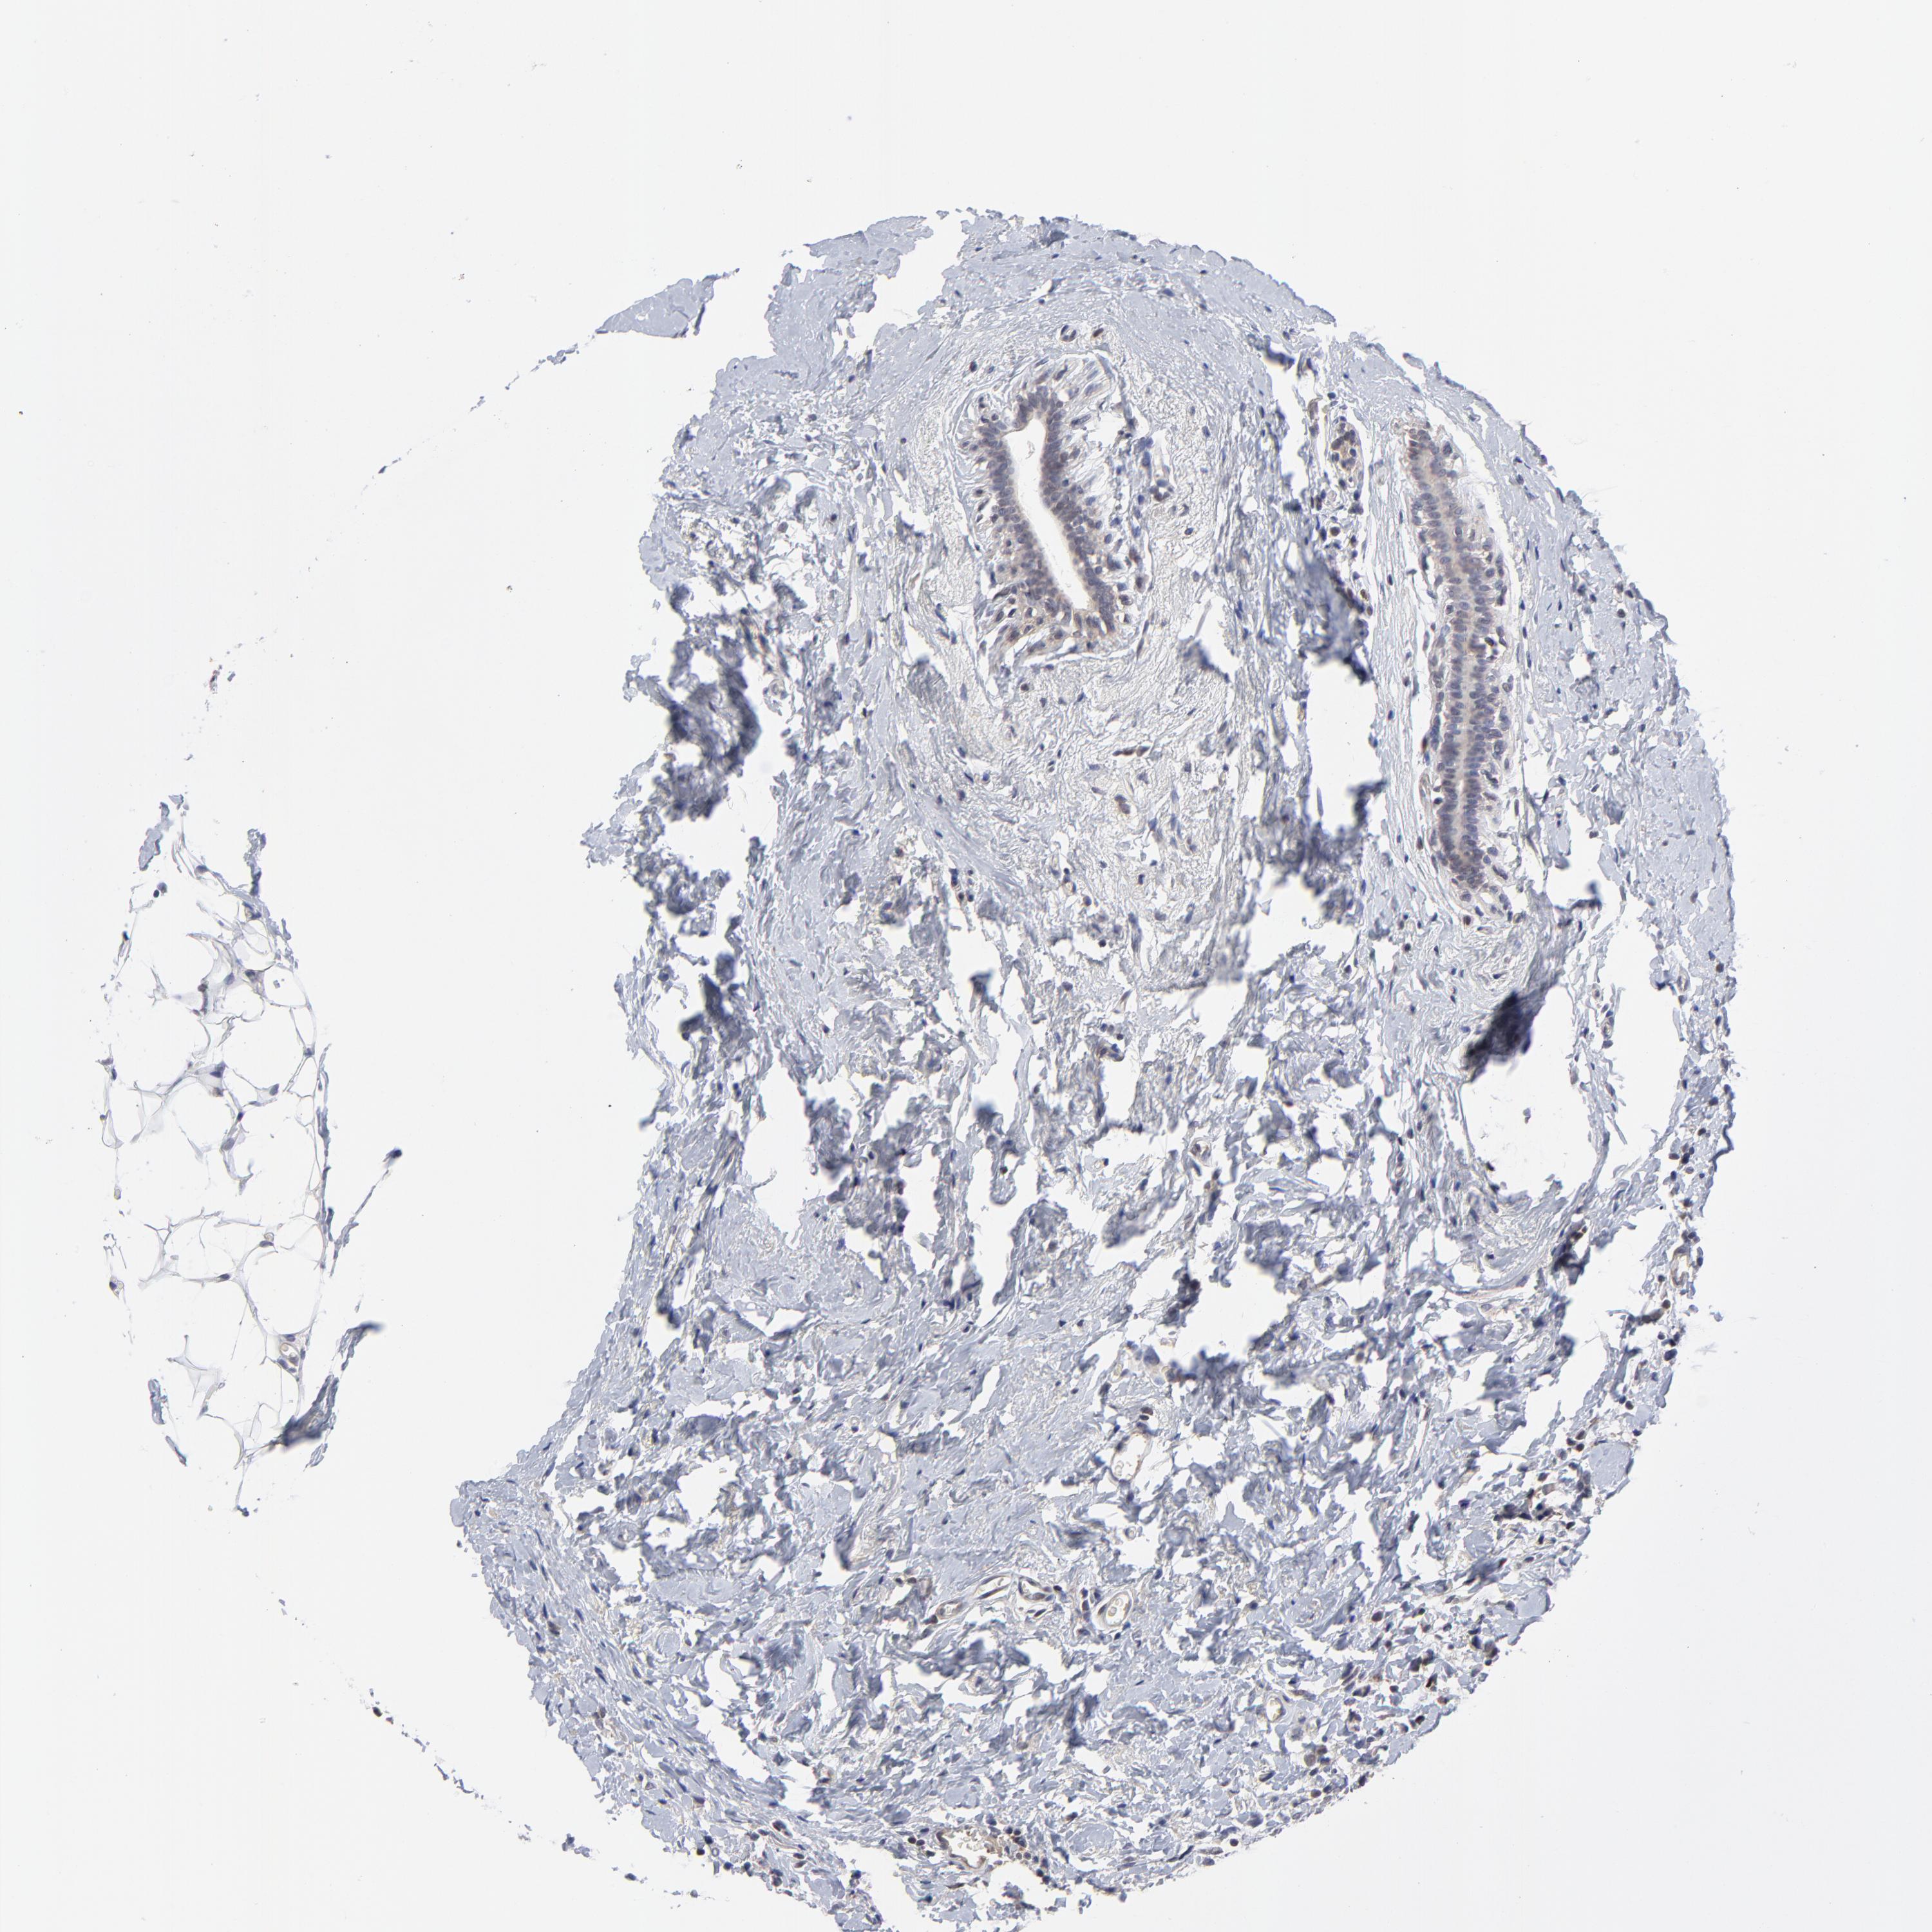

CANCER BREAST CANCER Show tissue menu

BRCA TCGA BRCA VALIDATION PROTEIN EXPRESSION